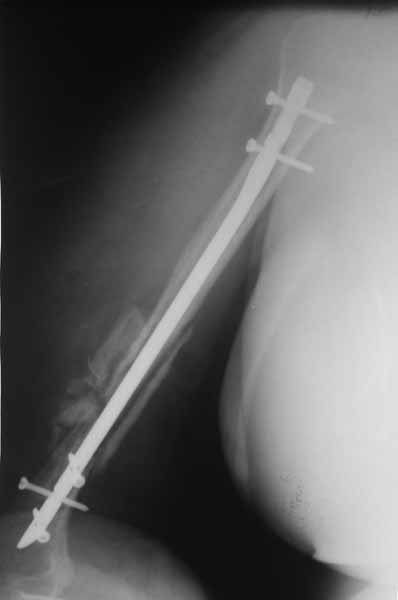

Сегодня пациентка поступила на этапное лечение. Жалобы на ограничение объема движений в плечевом суставе. Болевой синдром умеренный. Прошу совета в дальнейшей тактике лечения застарелого вывиха плечевой кости.

Есть мысль выполнить первым этапом артроскопический артролиз плечевого сустава и дня через 3-4 по купированию отека мягких тканей выполнить подвеску головки плечевой кости к акромиону аутотканями ( сухожилием, лентой из широкой фасции бедра и т.д.)

Плечевой сустав на сегодняший день спустя 10 мес. после травмы.

[ Ответить ]

Такое впечатление, что здесь не вывих, но сублюксация головки из-за длительного вынужденного положения, обусловленного особенностью первичного остеосинтеза.

Согласен с Антоном Бехтеревым- здесь скорее всего имеет место выраженная атрофия дельт и как следствие подвывих головки плеча.